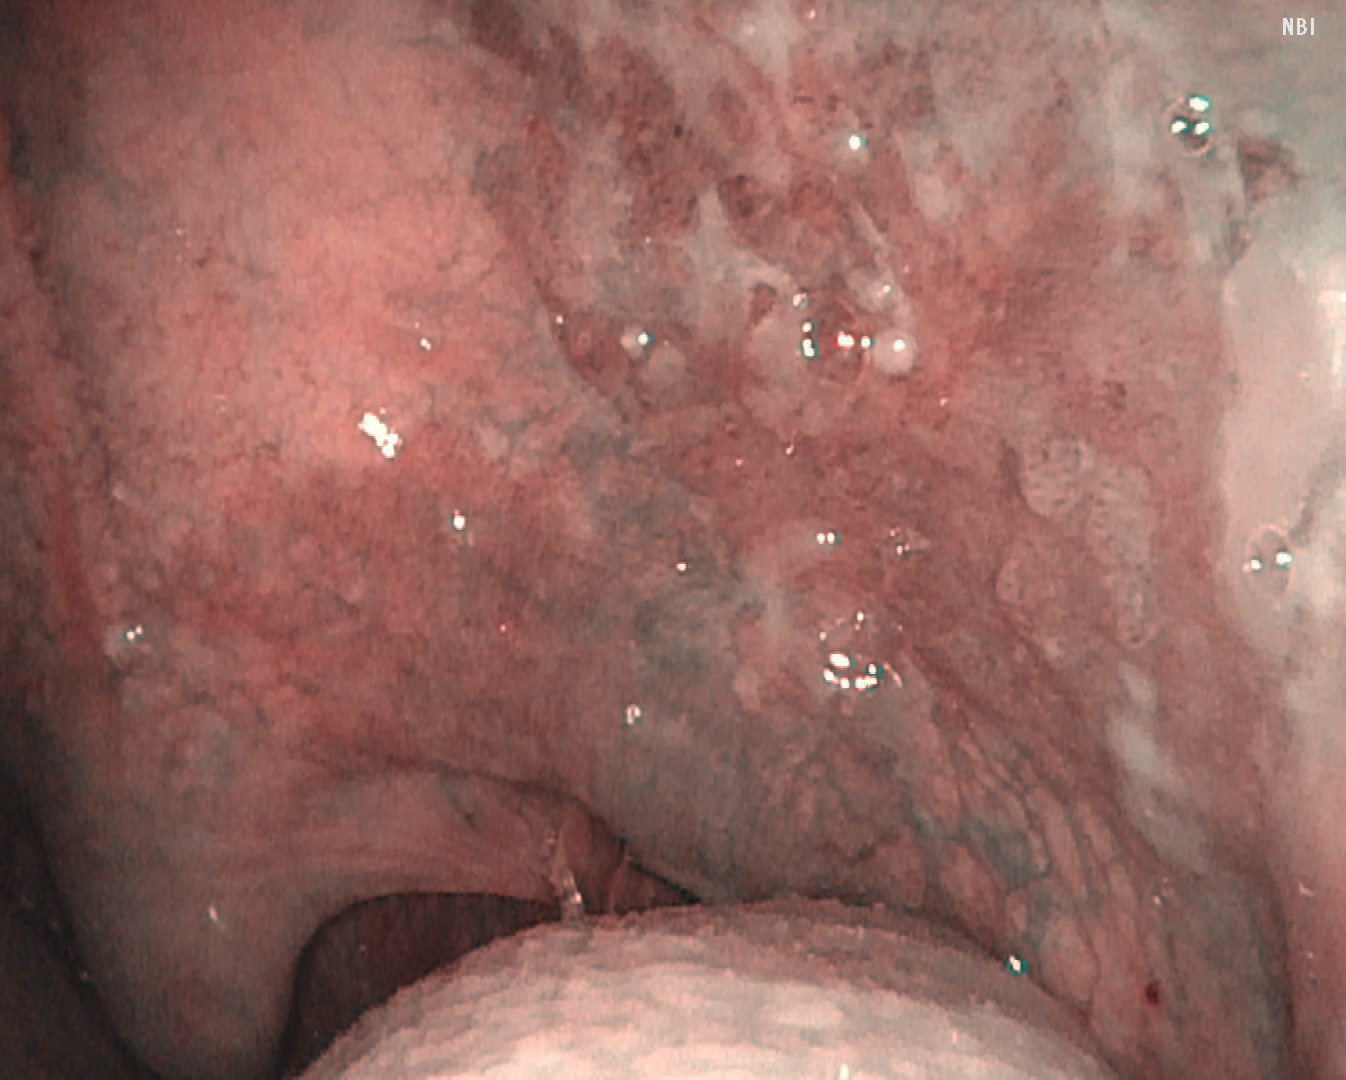

Case 1: Oropharyngeal Squamous Cell Carcinoma (cT1N0M0)

White-light observation revealed an erythematous lesion with an irregular surface extending from the left soft palate to the anterior palatine arch; however, accurate assessment of lesion extent was difficult. NBI observation demonstrated a well-demarcated brownish area with proliferative atypical microvessels. Compared with conventional systems (OTV-S190), VISERA S OTV-S500 provided enhanced contrast, allowing clearer delineation of tumor extension.

NBI Image

Video System Center: VISERA S OTV-S500

Video Rhinolaryngoscope: ENF-VH